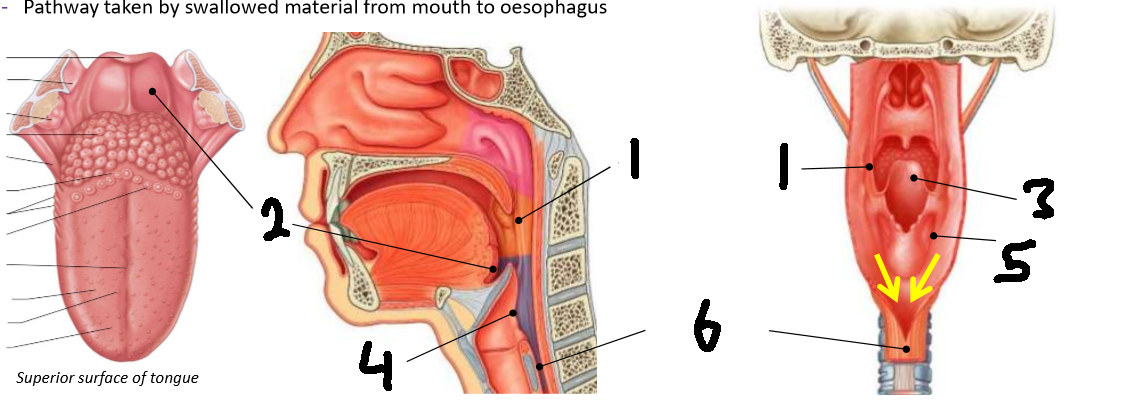

Which area of the head and neck do 1, 2, and 3 make?

pharynx

What region is 1?

nasopharynx

What region is 2?

oropharynx

What region is 3?

laryngopharynx

What is the anterior wall of 1?

posterior nasal choanae

What is the roof of 1?

body of sphenoid and basilar part of occipital

What is the posterior wall of 1?

anterior arch of atlas covered in pharyngobasilar fascia

What is the floor of 1?

soft palate

What is the horizontal dotted line?

pharyngeal isthmus

What is the vertical dotted line?

oropharyngeal isthmus

What is 1?

pharyngeal tonsil

What is 2?

pharyngeal opening of pharyngotympanic tube

What is 3?

tubal elevation

What is 4?

salpingopharyngeal fold

What is 5?

tubal tonsil

What is the anterior wall of 2?

oropharyngeal isthmus

What is the roof of 2?

soft palate

What is the floor of 2?

pharyngeal part of tongue and glossoepiglottic fold

What is the posterior wall of 2?

C2 and upper C3

What are the lateral walls of 2?

palatoglossal and palatopharyngeal arches

What is 1?

palatopharyngeal arch

What is 2?

vallecula

What is 3?

epiglottis

What is 4?

laryngeal inlet

What is 5?

piriform fossa

What is 6?

oesophagus